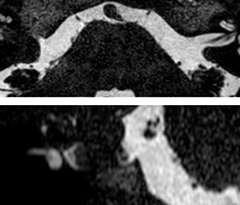

A two year follow-up scan of a CPA meningioma using both Ingenia 3.0T without CS and Ingenia Elition 3.0T with Compressed SENSE allows for a nice comparison to demonstrate the protocol improvements achieved on the Elition: 3D FLAIR has a shortened scan time, improved SNR and still the same spatial resolution. BrainView (3D T1 TSE) has improved spatial resolution and SNR with shortened scan time. For 3D T2 Drive the spatial resolution has been improved. 3D THRIVE used to have an interpolated 0.8 mm slice thickness, but true thickness at 1.6 mm, so that axial slices displayed a decent quality, but reformats were suboptimal.

Compressed SENSE is used on Elition to improve spatial resolution and reduce the non-interpolated slice thickness to allow smoothly reformatted images. Total scan time (adding SmartBrain and an additional b2000 diffusion) was 13:19 on Ingenia, and is now reduced to 10:42 on Ingenia Elition.

Ingenia 3.0T (without Compressed SENSE)

3D FLAIR (without Compressed SENSE)

3D FLAIR

1.0 x 1.0 x 1.0 mm*

4:24 min.

3D TSE T1w (without Compressed SENSE)

3D TSE T1w

1.0 x 1.0 x 1.2 mm*

2:40 min.

3D T2w Drive (without Compressed SENSE)

3D T2w Drive

0.8 x 0.8 x 1.0 mm*

3:05 min.

3D T1w THRIVE (without Compressed SENSE)

3D T1w THRIVE

0.8 x 0.8 x 1.6 mm*

1:30 min.

Ingenia Elition 3.0T with Compressed SENSE

3D FLAIR (with Compressed SENSE)

2:50 min.

3D TSE T1w (with Compressed SENSE)

2:10 min.

3D T2w Drive (with Compressed SENSE)

0.7 x 0.7 x 0.7 mm*

2:52 min.

3D T1w THRIVE (with Compressed SENSE)

0.7 x 0.7 x 0.8 mm*

*true voxel size, without interpolation